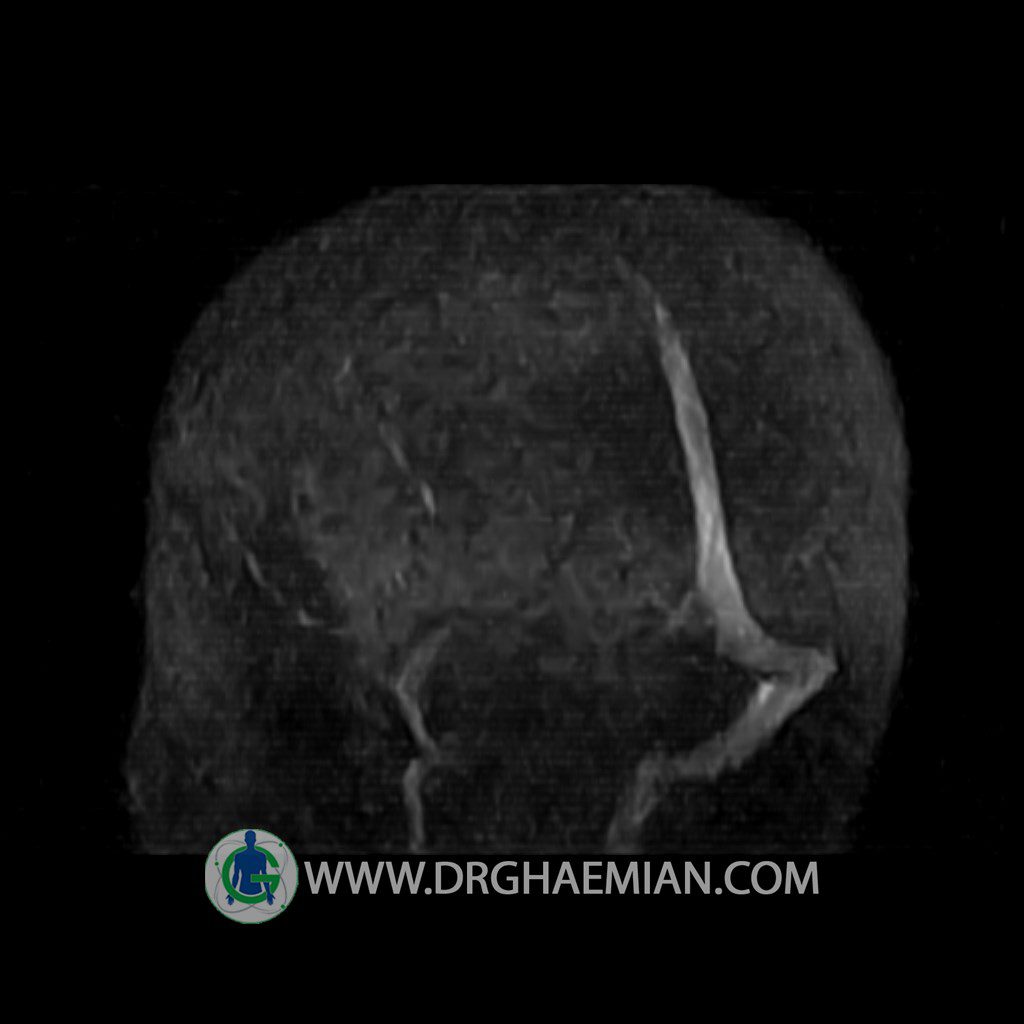

ام آر وی یک روش تصویربرداری دقیق و غیر تهاجمی است که برای معاینه ورید های بدن و ارزیابی سلامت رگ ها استفاده می شود. ورید ها خون را از اعضای بدن به قلب باز می گرداند تا دوباره اکسیژن و مواد مغذی به خون داده شود. ام آر وی جریان خون را ارزیابی و موارد غیرعادی مضر مانند لخته های خونی را شناسایی می کند. در این کیس ترومبوز دیواری مغز در سینوس عرضی راست و ترمبوز جزئی در سینوس عرضی چپ دیده می شود.

Technique: TOF ( time of flight ).

Images of the venous cranial vessels demonstrates a superior sagittal sinus of normal caliber with normal arrangement of draining superficial cerebral veins.

The great cerebral vein Galen inferior sagittal , straight sinus and left sigmoid sinus appear normal.

The right sigmoid sinus present a normal caliber.

The other evaluable deep cerebral veins , basal and labbe are normally developed and patent.

– Narrowing of left transverse sinus with filling defect & inthimal irregularity

suggestive for partial thrombosis

– Inthimal irregularity in anterior wall of right transverse sinus suggestive for mural thrombosis

are seen